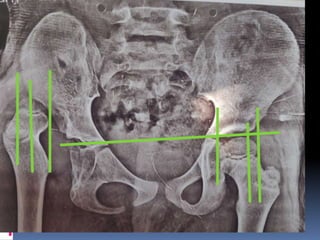

Intraoperative fluroscopic shot of left adductor

release, femoral varus osteotomy, and dega

osteotomy.